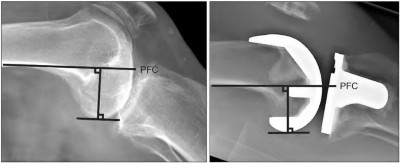

A 72-year-old female presents with progressive left thigh and knee pain for the last year. 5 years ago she sustained a femoral neck fracture treated with the implant seen in Figures A-C (current radiographs). The thigh pain is worse with weight-bearing. C-reactive

protein and erythrocyte sedimentation levels are within defined limits. Which of the following is the most likely cause of her pain?